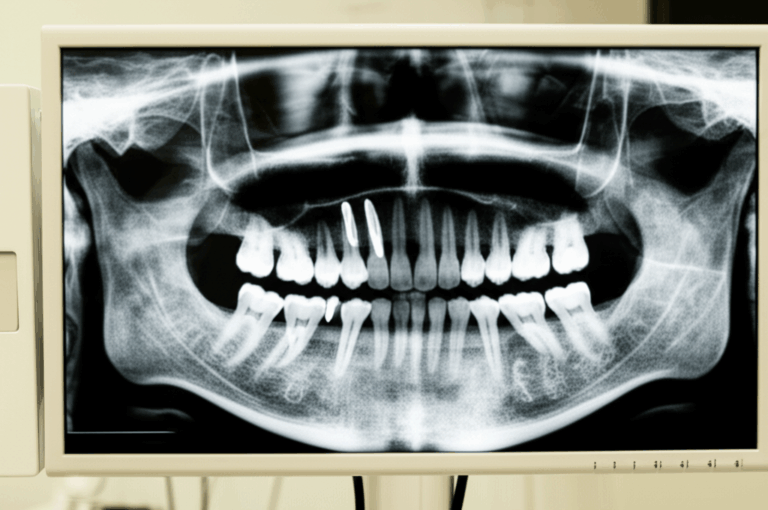

- Exam and X-rays or CT scans